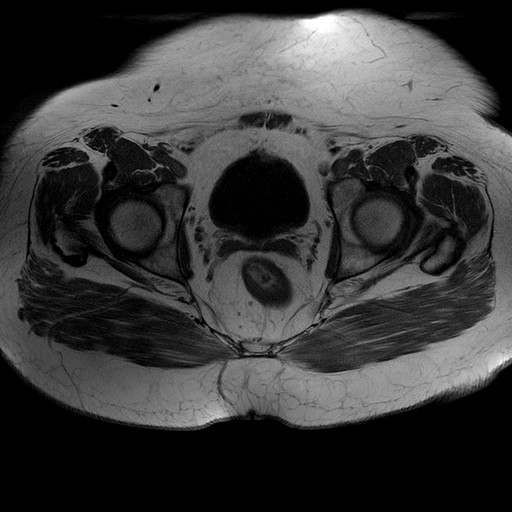

Esami: RMN BACINO

T1W_TSE

Evidenti e simmetriche alterazioni osteofitosiche in regione coxo femorale con riduzione delle rime articolari. Degenerazione completa del cercine glenoideo. Non attuali segni di versamento articolare. Non segni di edema osseo che escludono attuale algodistrofia od osteonecrosi. Lieve e simmetrica riduzione del trofismo della muscolatura glutea.